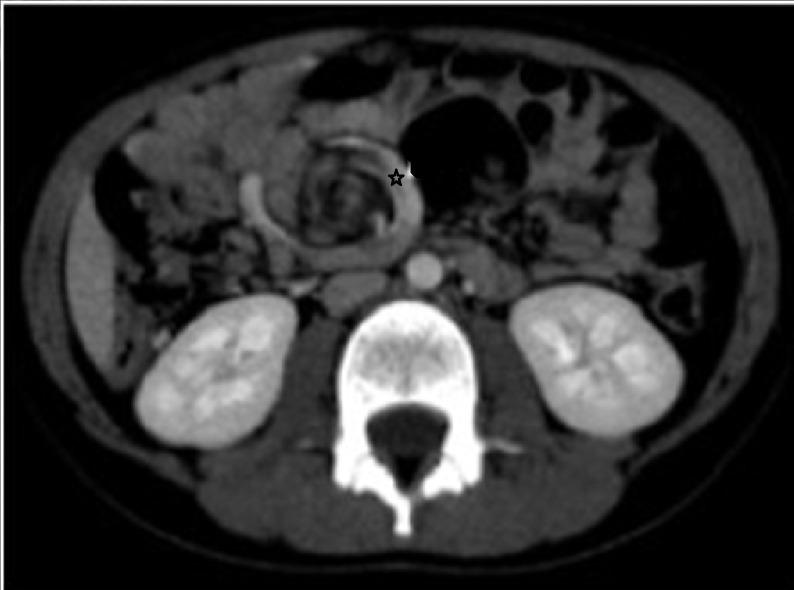

Gastrointestinal duplications can affect any part of the alimentary tract and are notorious for their variable presentation. Their association with malrotation and midgut volvulus is rare. We describe an 8-year old boy presented with episodes of abdominal pain. Radiological workup showed whirlpool sign and abnormal relationship of mesenteric vessels. At operation, malrotation with chronic volvulus was found. Incidentally, a jejunal communicating duplication cyst was also noted.

胃肠道重复畸形可累及消化道的任何部位,其临床表现多样,因而声名狼藉。它们与肠旋转不良和中肠扭转的关联较为罕见。我们描述了一名8岁男孩,他出现腹痛发作。影像学检查显示有漩涡征及肠系膜血管关系异常。手术时发现存在伴有慢性扭转的肠旋转不良。偶然间,还发现了一个空肠交通性重复囊肿。